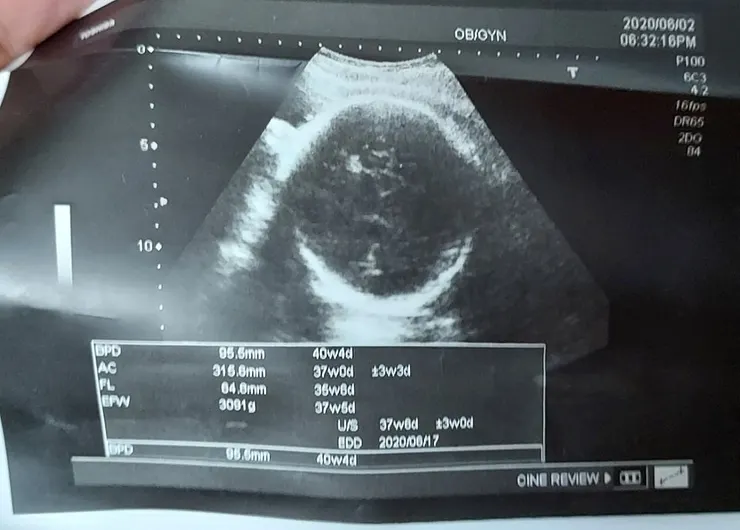

2020.6.04(四)AM11:00 (6.2--34W 3091G)

還好網路上有這些介紹 一知半解滿恐怖的,週二去做兩周一次的產檢,兩周前還是2411,本周34周來到3091,一般網路上看到都是2500左右,醫生說頭怎麼大這快 已經9.5CM 大了六周,六周都可以生的頭了 太可怕,有點緊張是不是甚麼大頭症,還是唐氏症,因為想說反正有沒有唐寶寶都要生 就沒羊膜穿刺了,但是聽到結果還是挺可怕了,不過淡定的醫生說再觀察看看 也許之後就不會在大了,也說我比較高有可能生大隻一點的,但還是有點小擔心,不過網路上看到一些孕媽咪,好像也有說超音波也有不準的 心情有被安慰到了,有的是被告知寶寶過大 但是生出來其實還好,不然就是看起來正常 但是生出來過大。

另外和大家分享一下今天產檢終於沒有這麼嚇人了,上次34週說寶寶3091克 頭95.5頭大了四週,因為32-34多了六百克,嚇死我了,30-32很努力吃燕麥才多了300克 後來放鬆一點吃了冰淇淋,布丁 豆花 但是真的都也只吃一點 還是多了600太恐怖,所以34-36週這兩星期我也很努力吃燕麥,今天的數字是 3297克 頭圍 95.9 天阿太幸運了,雖然之前大家都安慰我會有誤差 但是還是會緊張,我也努力相信有誤差 讓自己平安,雖然目前數字自己覺得可以接受 但是表示接下來還是要努力祈禱和克制 進行燕麥人生 超級超級感謝天主,也請大家繼續為我的順產祈禱 因為我真的覺得我是史上最怕痛的女孩。